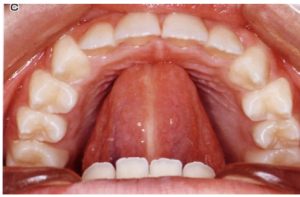

1、スポットポジション <舌の先をいつも置いておく位置を覚える>

スポットポジション

舌の先を置いておく位置

スポット

スティックをスポットに当てる。

次に舌の先をスポットに当てる。